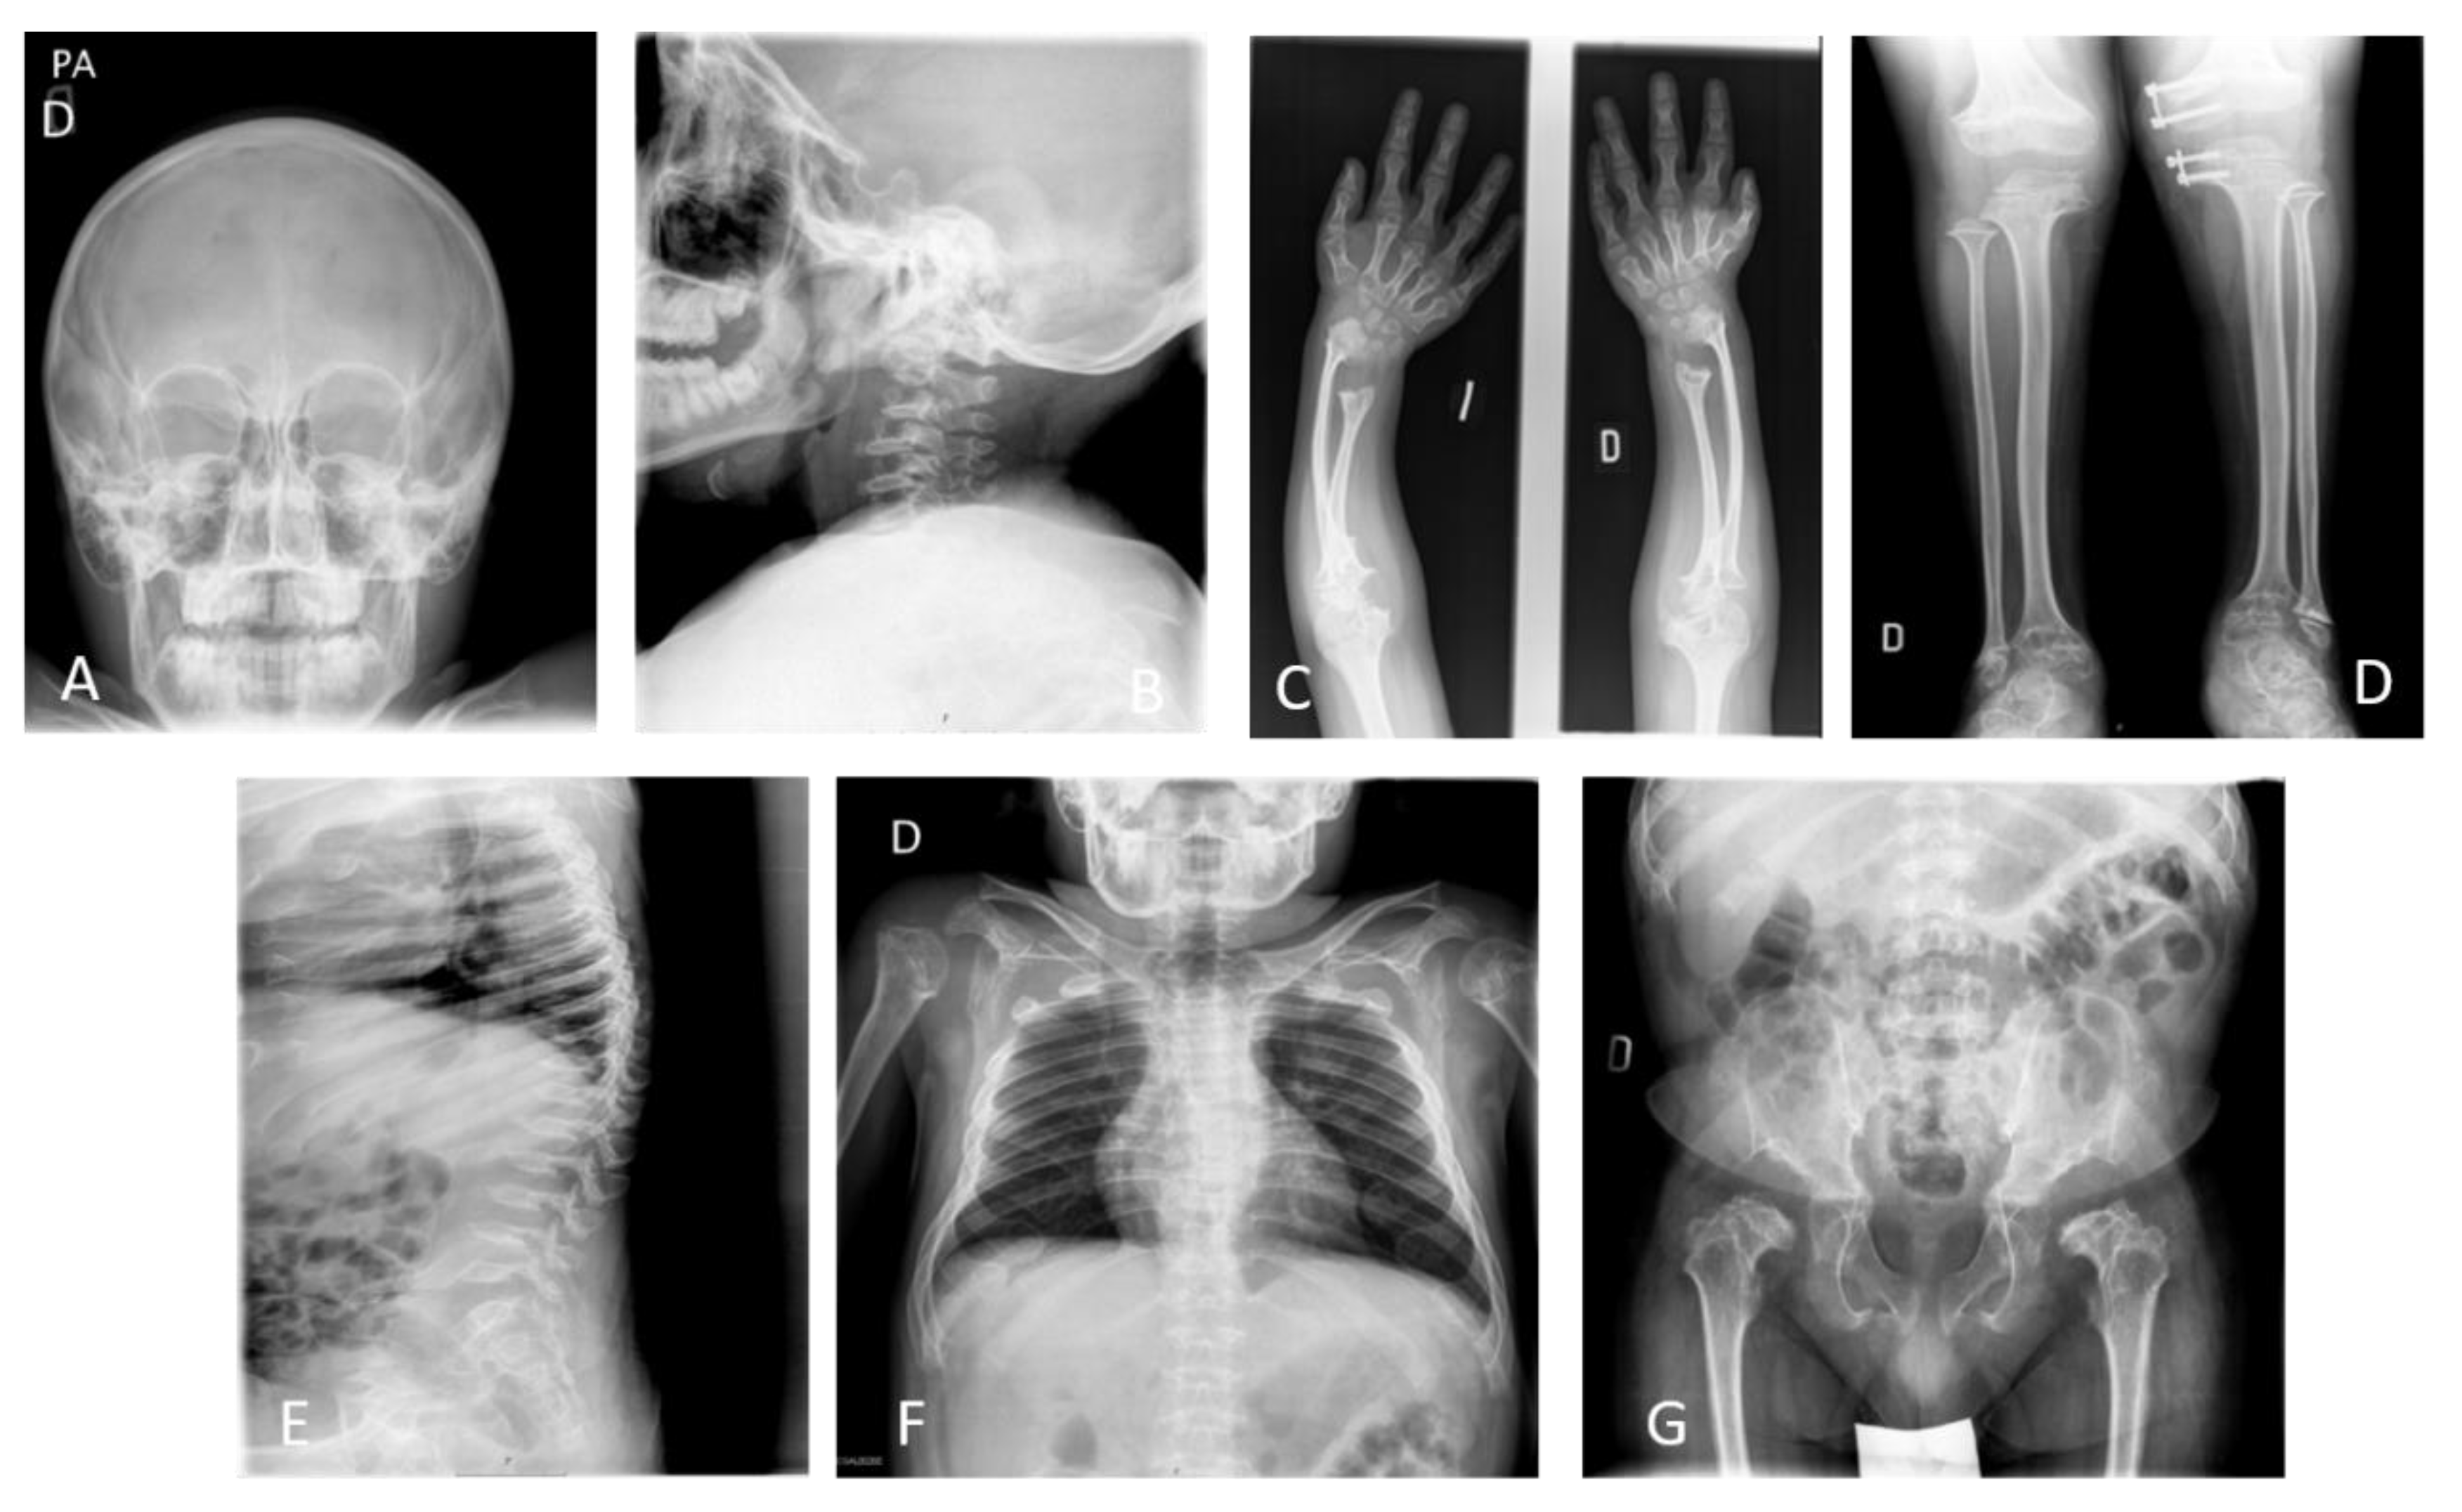

2.3. Radiographic Diagnosis